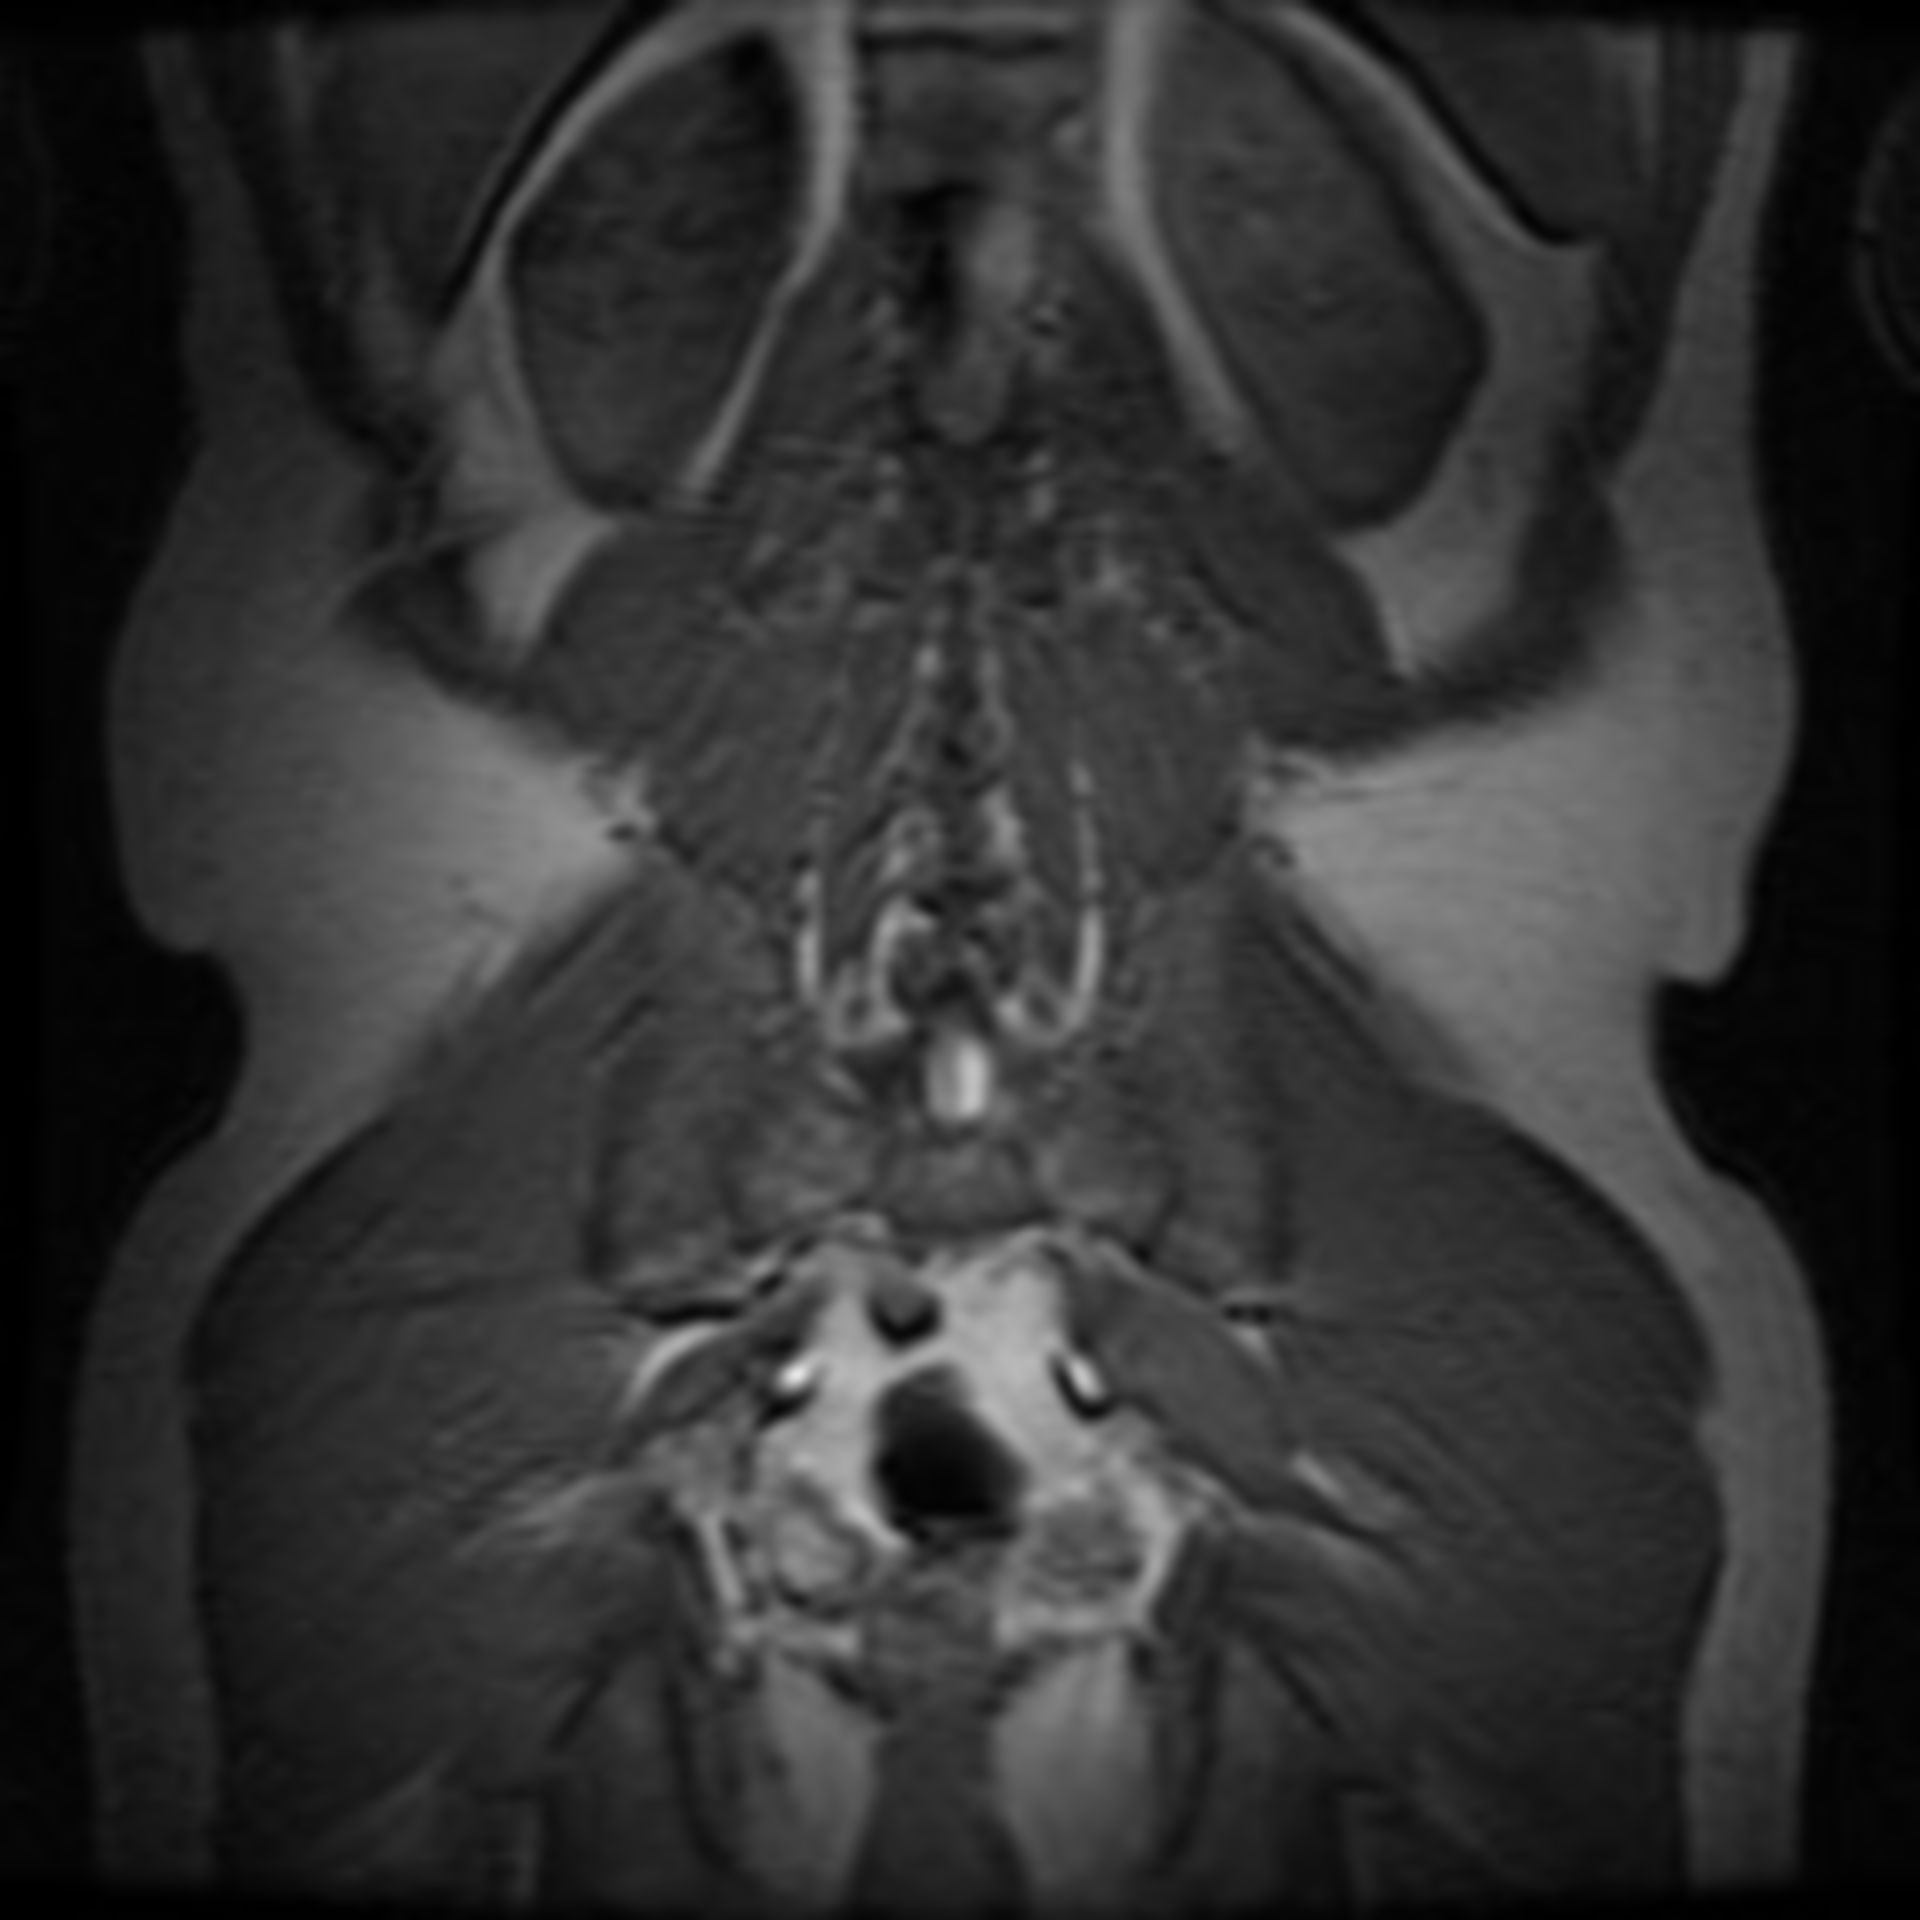

MRT Übersichtsaufnahme – DocCheck MRT Schädel – DocCheck

MRT abdomen – DocCheck MRT Knie links

Mrt bild deuten (Wirbelsäule, Radiologie) Glioblastom in der MRT,T1-gewichtet mit Kontrastmittel, sagitaler Schnitt aus dem KGU | Kampf …

MRT Thorax – DocCheck Abb. 2 9 Charakteristische MRT-Befunde bei der autosomal-rezessiven… | Download Scientific Diagram